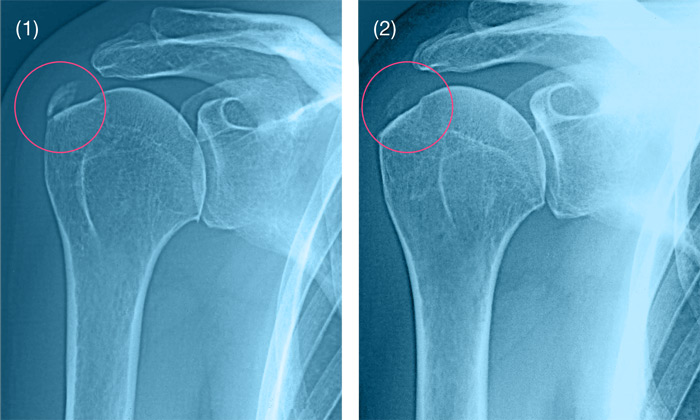

Оссификаты Локтевого Сустава: Диагностика и Лечение

Раздел: Секреты мастерства